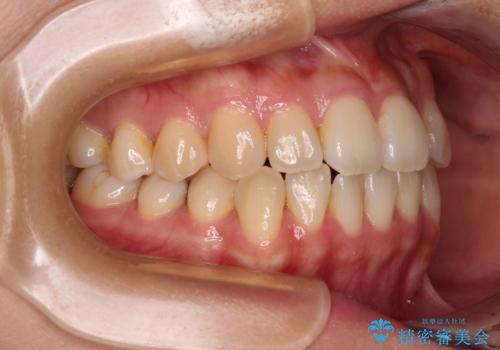

左下の奥歯は根管治療後に放置されていたため、咬み合わせを調整しながら矯正治療を行い、最後にオールセラミッククラウンにて補綴治療を行うこととしました。

舌のトレーニングをしっかりと行っていただき、補綴治療も含めて1年強の短期間で治療を終えることができました。